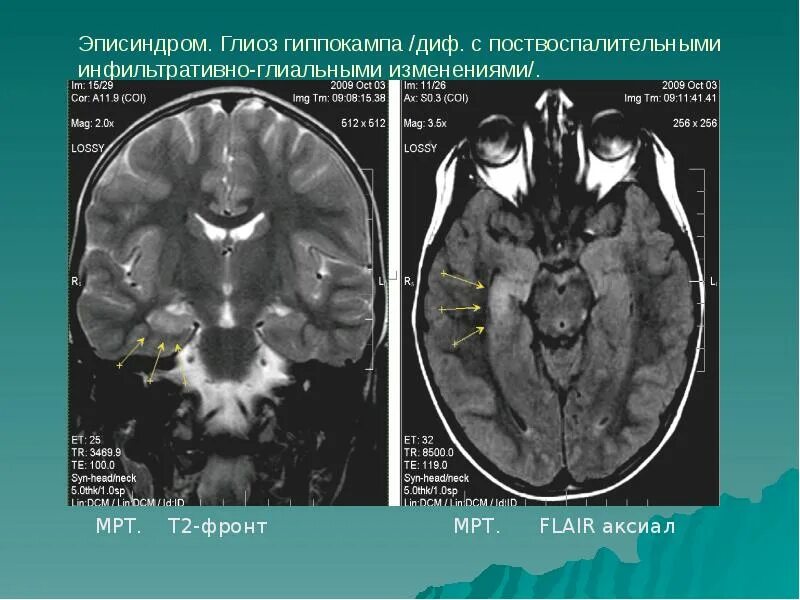

Эписиндром у взрослых